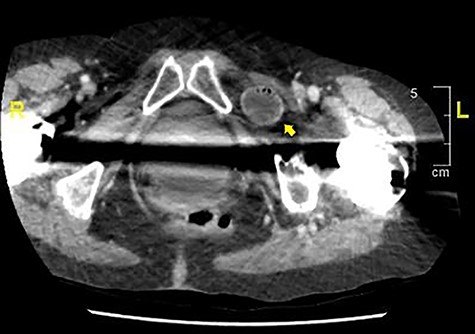

On initial presentation, her blood results were as follows: white cell count (WCC) 14.8 × 109 cells/l (RR 4.3–11.2 cells/l), neutrophils 12.3 × 109 cells/l (RR 2.1–7.4 cells/l) and C-reactive protein (CRP) 1.9 mg/l (RR 0–5 mg/l). Imaging performed included an abdominal film, which showed nonspecific bowel gas pattern (Fig. 1). The patient was managed conservatively and discharged home. She represented 2 days later with worsening symptoms and blood results of WCC 20.1, neutrophils 18.4 and CRP 6. She was admitted under the surgical team and a thoracic and abdominal CT scan was done (Figs 2–4). It was initially reported as significant dilated small bowel loops in keeping with small bowel obstruction due to a femoral hernia. However, the scan was revisited by the surgical team in more detail as the images appeared to represent an obturator hernia. Upon further discussion, these findings were corroborated by the radiologist and a strangulated left obturator hernia was identified.

Axial section demonstrating small bowel loops in left obturator space.